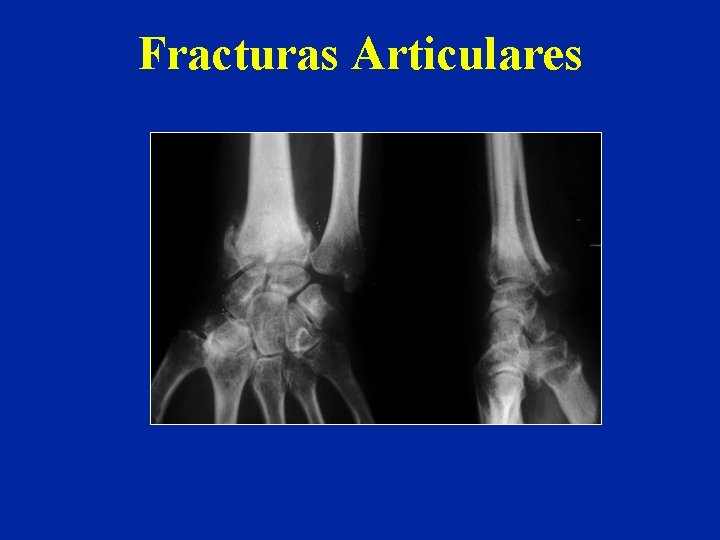

Fracturas Articulares